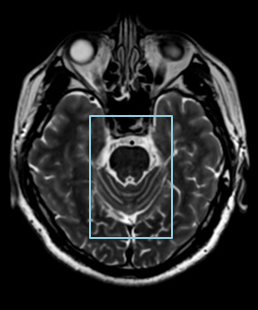

PIQE for MR

极速高分辨率成像

在磁共振领域,深度学习技术对图像进行降噪、上采样、减轻振铃伪影的处理,带来了清晰且细节丰富的图像。

过去,高分辨率图像的获取往往伴随着漫长的扫描时间,这影响了图像获取的效率,对于危重疾病的快速诊断是一大挑战。然而,PIQE技术的出现彻底颠覆了这一局面。此次发布的全新3T磁共振Galan Supreme,搭载全新的自研磁体和梯度线圈,并深度融合PIQE技术,可以实现在不增加扫描时间的前提下,轻松获取到高分辨率的图像,为临床带来了兼具高效与高质量的影像体验。